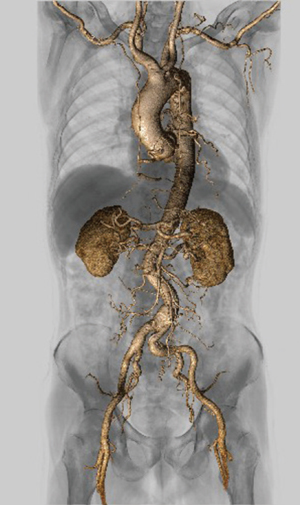

図3 大動脈解離

高速ヘリカルスキャンとAbierto Visionで

全身血管を描出

同院では、重症外傷などの救急患者は治療を優先してハイブリッドERで対応している。稲垣係長は、「初期治療後の全身状態の精査はADCTで撮影を行っていましたが、Aquilion ONE / INSIGHT Editionの高速撮影やPIQE、CLEAR Motionなどによって、全身浮腫や息止め不可といった状態の悪い患者でも診断に寄与する画像が提供できるのではと考えています」と述べる。